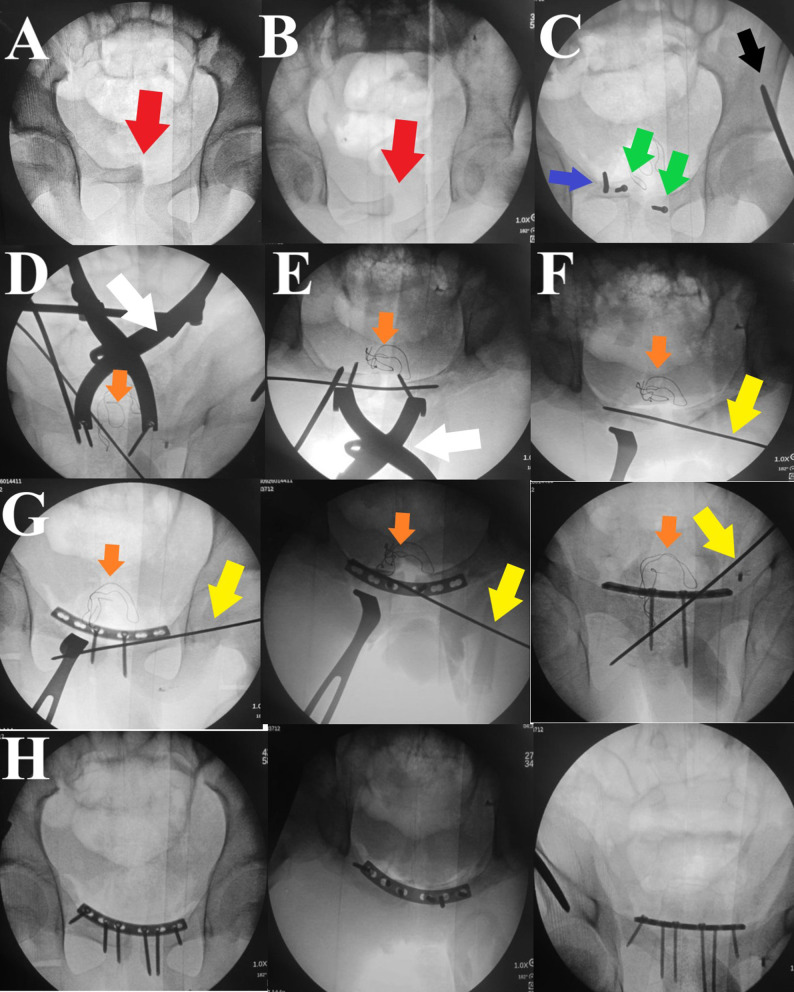

Urinary bladder entrapment or incarceration within pelvic fracture have been described in many reports in the literature, most of which were reported in adult patients. We describe a case of a 14-year-old boy presented with isolated locked symphysis pubis disruption after falling from a height. His initial evaluation was negative for any other associated injuries. The decision was made to treat him surgically by open reduction and internal fixation using a symphyseal plate; however, upon completing the Pfannenstiel incision, the surgeon faced a soft tissue mass hindering bony fragment dissection; upon careful examination, the soft tissue mass turned out to be entrapped urinary bladder within the symphyseal disruption. After careful soft tissue dissection, and with the help of Jungbluth distractor, the disruption was over-distracted, the bladder was freed entirely (which was intact) and reduced to its position, followed by the application of a symphyseal plate in a reduced symphysis pubis position. The patient did well postoperatively, and at three months follow up, the disruption and fracture united, and there were no urinary-related symptoms. Although rare, urinary bladder entrapment within an element of anterior pelvic fracture could be a reason for the difficult reduction; careful evaluation and steady soft tissue dissection are paramount for avoiding undue iatrogenic urinary bladder injury.